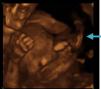

Caso clínicoGestante de 29 años, con el antecedente de legrado obstétrico por aborto espontáneo de primer trimestre, que acude a la Consulta de Diagnóstico prenatal para realizar el cribado de aneuploidías fetales, con una edad gestacional de 12 semanas. En la ecografía se visualiza un embrión acorde a la edad gestacional, con latido cardiaco positivo y la presencia de una estructura hiperecogénica, sin flujos vasculares en su interior, que surge de la pared amniótica y afecta al miembro inferior distal derecho, presentando una movilidad espasmódica del tercio medio inferior de la pierna, con pequeños movimientos de flexoextensión, pero con una movilidad reducida por la brida. Dicha brida se adhiere además a la cara anterior abdominal y a uno de los brazos (figs. 1-5). Se repite la ecografía a la semana, comprobando los mismos hallazgos y ante el mal pronóstico la paciente decide interrumpir la gestación.